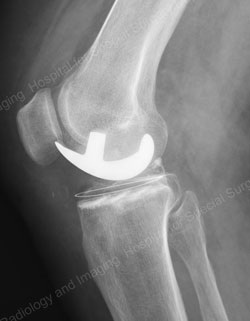

Figure: Example of a fixed bearing unicondylar knee replacement

(the images on top represent a preoperative joint; the images on the bottom represent a postoperative joint)